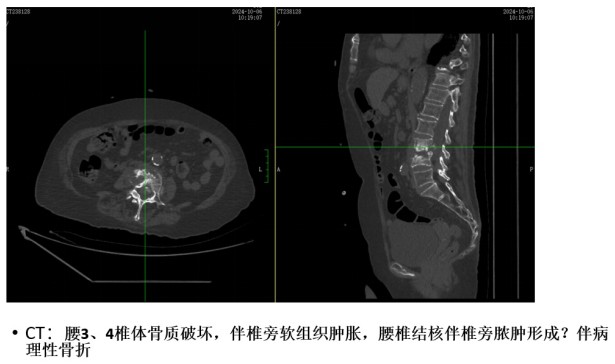

為解決老人病痛���,脊柱外科錢軍博士團(tuán)隊(duì)對(duì)其進(jìn)行了詳細(xì)的查體以及全面細(xì)致的評(píng)估�����,診斷為L3�����、4脊柱結(jié)核伴病理性骨折���、椎旁膿腫����,患者腰部疼痛癥狀逐漸加重�,病灶已經(jīng)壓迫神經(jīng)引起了截癱�。